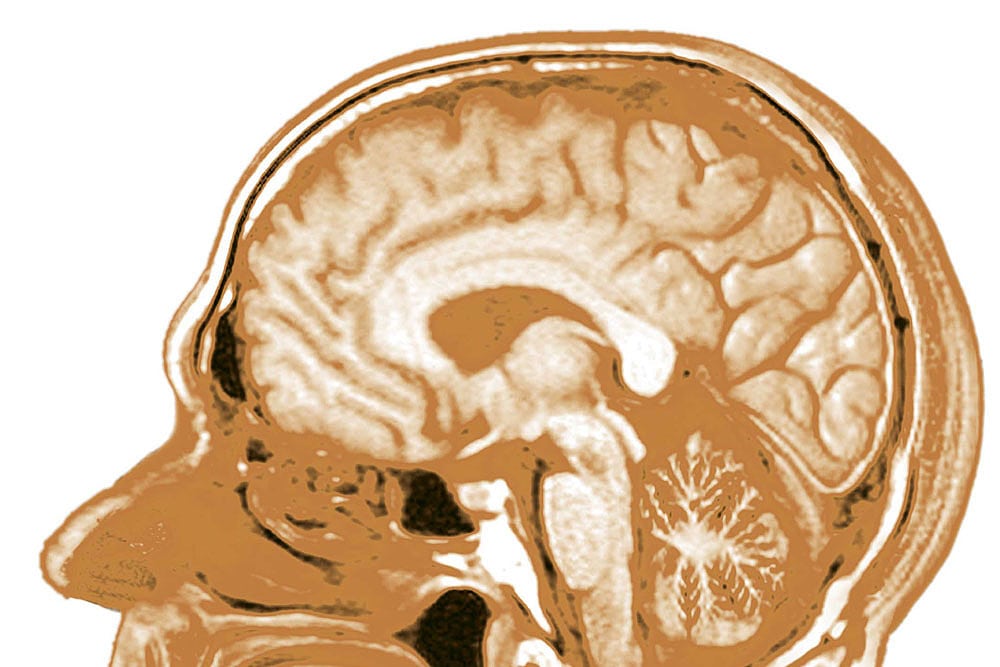

"In den letzten Jahren ist unser Verständnis des Gehirns dramatisch gewachsen. Trotzdem müssen wir noch viel lernen. Millionen Menschen leiden an neurodegenerativen Erkrankungen, an Schlaganfällen, Autismus und anderen Störungen. Diese Menschen und ihre Familien haben Grund zur Hoffnung: Fortschritte in der Genetik und bildgebenden Hirnforschung eröffnen Ärzten und Forschern immer bessere Einblicke."

Heute, im Jahr 2014, stehen die bildgebende Hirnforschung, die Neurodidaktik sowie die biologisch orientierte Psychiatrie oft in der Kritik. Unbeeindruckt davon bekräftigte die EU-Kommission sowie die US-Regierung mit zwei Paukenschlägen die besondere Rolle der Neurowissenschaften: Die Europäer riefen das milliardenschwere Human Brain Project (HBP) aus, und die Amerikaner konterten mit ihrer BRAIN Initiative. Beide wollen helfen, den Geheimnissen des Gehirns auf die Spur zu kommen (siehe GuG 1-2/2014, S. 36).